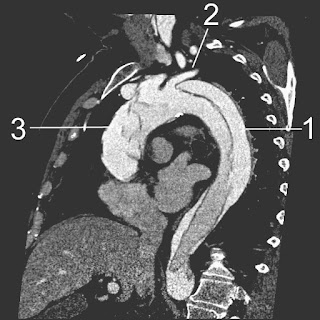

This systematic review and meta-analysis aims to determine the diagnostic accuracy of D-dimer as a rule out test for acute aortic dissection. The overall results showed a sensitivity of 98% and negative LR of 0.05 (with little statistical heterogeneity) and a poor specificity of 41.9% and LR + 2.11 (with significant statistical heterogeneity). One major limitation of this study included publication bias (file drawer effect). Until a clinically validated tool is available to accurately evaluate the pre-test probability for aortic dissection, we should be very cautious in relying in a negative D-dimer result to exclude this diagnosis.